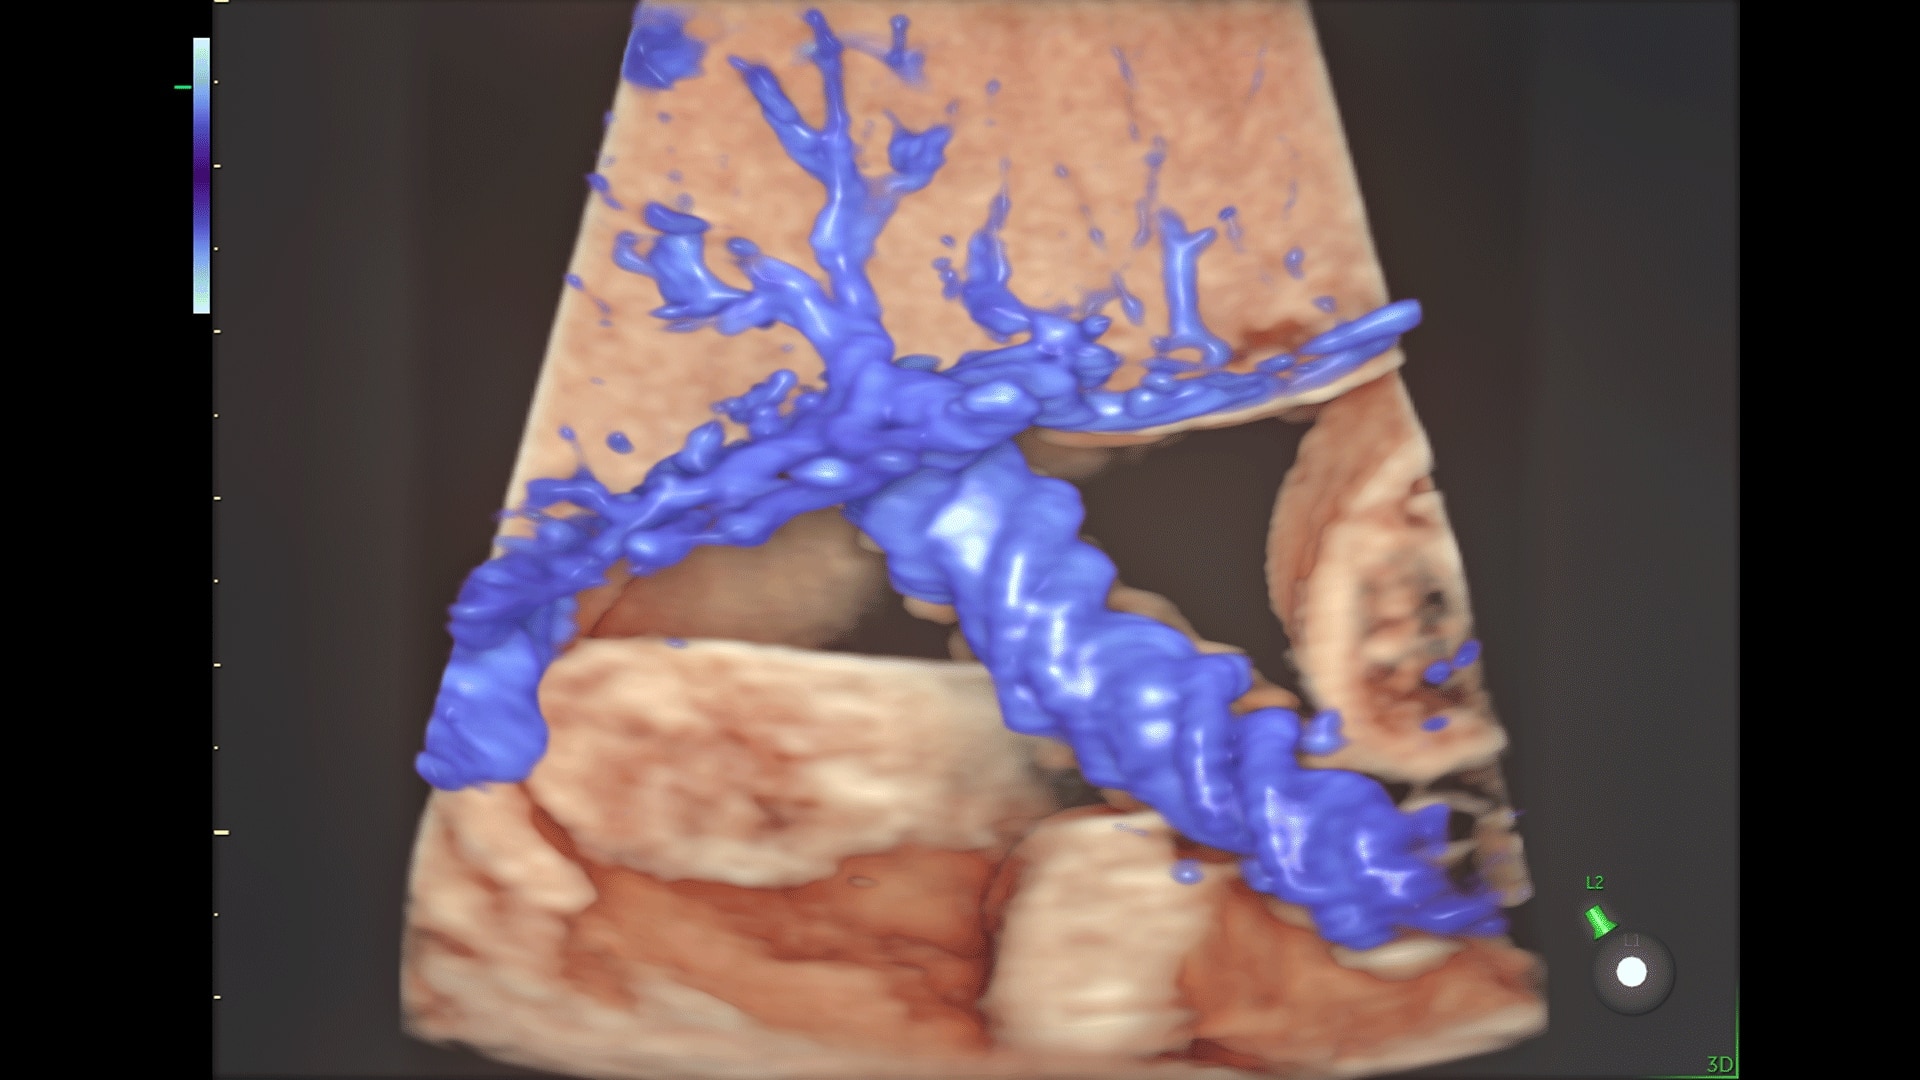

Generate spectacular 2D/3D and color Doppler images with increased penetration and stunning clarity, to help visualize critical details needed for diagnostic assurance. The Lyric Architecture unlocks new imaging and processing power to expand your imaging capabilities for years to come